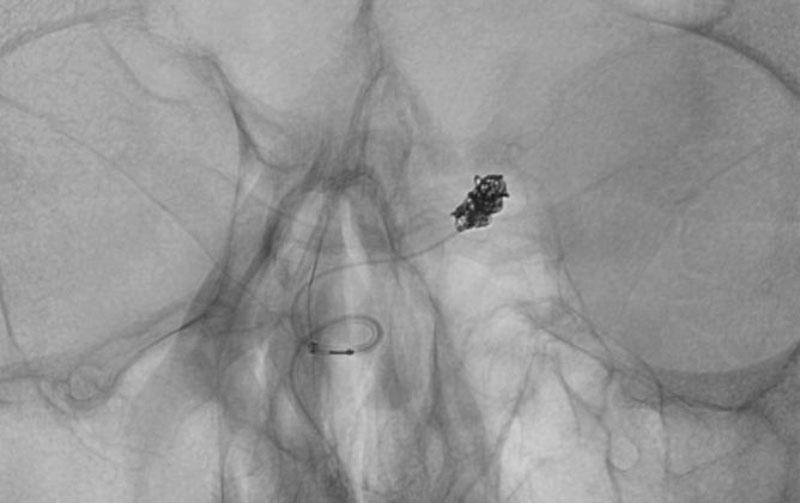

'25年10月

くも膜下出血

前交通動脈瘤破裂

60代

救急外来

No.1588 手術前

No.1588 手術中

No.1588 手術後